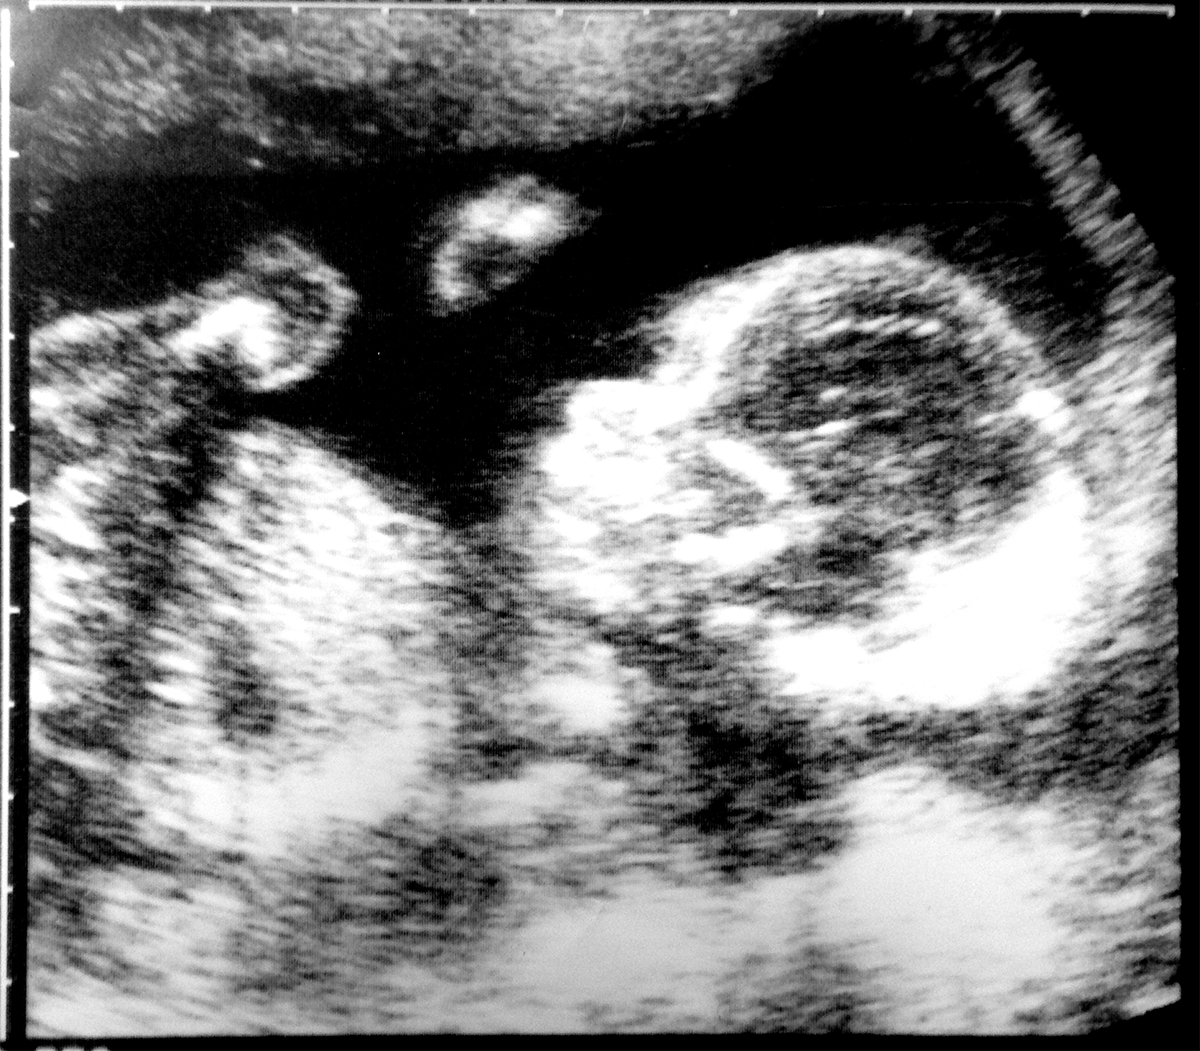

Week 8-24

The foetal phase starts at the end of week 8. During this time, the body's organs and tissues continue to grow and will start to work. The foetus will grow in length through the second trimester to 24 weeks gestation.

By 24 weeks gestation, the foetus will have developed sufficiently that it is possible for the baby to be born and to be viable or live outside the mother's uterus. This is only possible because the last body system to develop functionality, the respiratory system, starts to develop its functionality around weeks 21-23. Currently the earliest known live birth of a baby who survives into childhood is a baby born around 22 week's gestation.